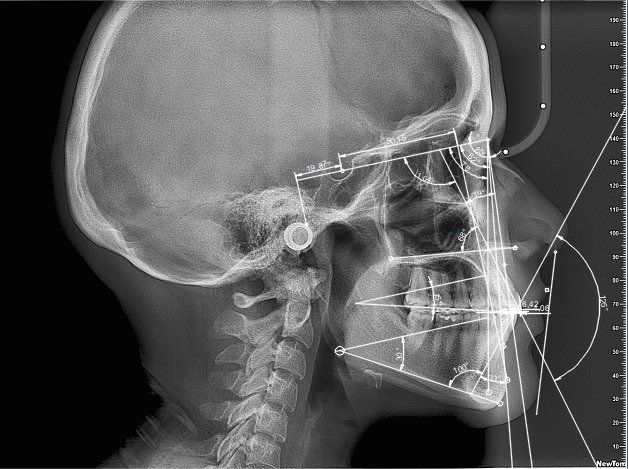

- Cefalometría I

- Cefalometría ll

- Cefalometría lll

- Cefalometría lV